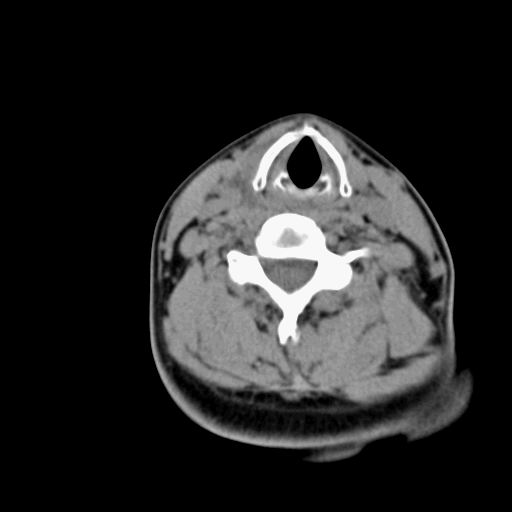

标题: CT23947 右颈部触及00.5x1.5cm质硬长形肿块,疼痛 [打印本页]

标题: CT23947 右颈部触及00.5x1.5cm质硬长形肿块,疼痛

右侧甲状腺病灶,建议增强或结合b超检查。

甲状腺右叶占位病变,建议增强扫描。

甲状腺占位  定性有时很难 但无论癌还是腺瘤 还是手术比较好!以下是甲状腺占位的ct鉴别诊断

ct表现:形态不规则的软组织密度肿块,可累及部分或大部分甲状腺组织,密度不均,可坏死、囊变、钙化,增强病灶呈不均匀强化,有局部侵犯或转移时可有颈部淋巴结肿大。

ct表现肿瘤呈稍低密度结节状肿块,边缘光整、锐利病灶均匀强化,少数腺瘤可有钙化。

ct表现:甲状腺弥漫性增大,边缘清楚,密度均匀或不甚均匀,增强扫描有强化。结节状甲状腺肿尚可见在增大的甲状腺组织内有多发结节状低密度或高密度区,并常多发性钙化。